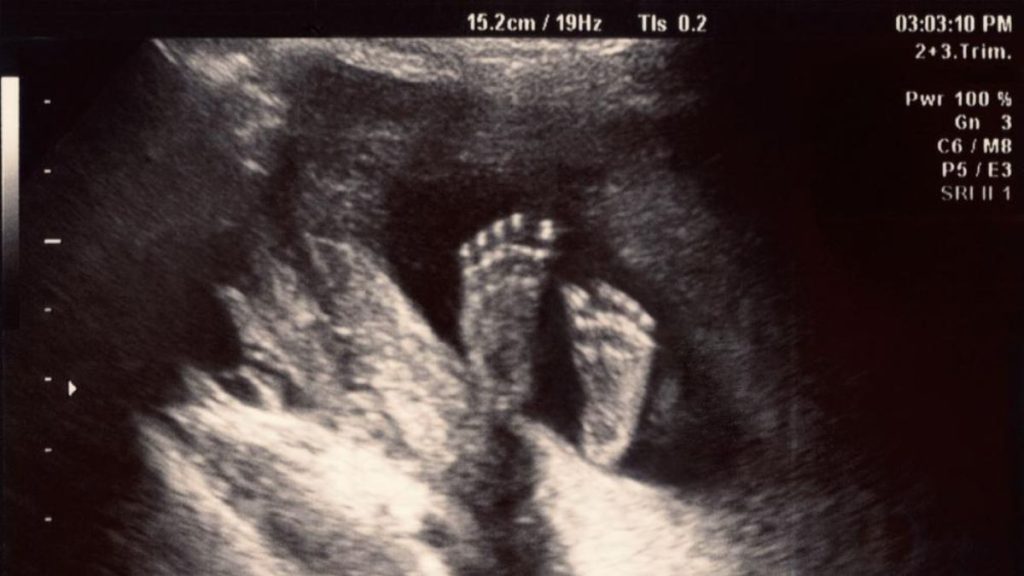

Mas durante seu ultrassom de 30 semanas, Kenyatta descobriu que sua filha tinha uma condição rara conhecida como malformação da veia de Galeno.

Na verdade, quando o bebê tinha 30 semanas, seu coração estava lutando e a malformação estava ficando perigosamente grande, relata a CBS .